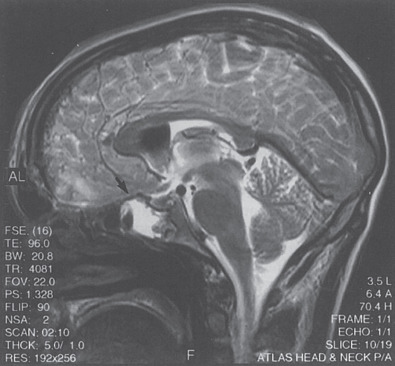

Magnetic Resonance Imaging (MRI)

For cases in which clinical uncertainty exists regarding actual CSF leakage or where further anatomic clarification of potential leak sites would be beneficial further imaging studies may be indicated on a case-by-case basis. Multiplanar fine-cut T2-weighted MR imaging can reveal CSF accumulation into particular paranasal sinuses and even the site of potential dural tears or pseudo-meningoceles (see Fig. 1.6.2 ). This information can be invaluable for clinical decision making and planning the surgical approach (open vs. endoscopic) one takes for a particular case.